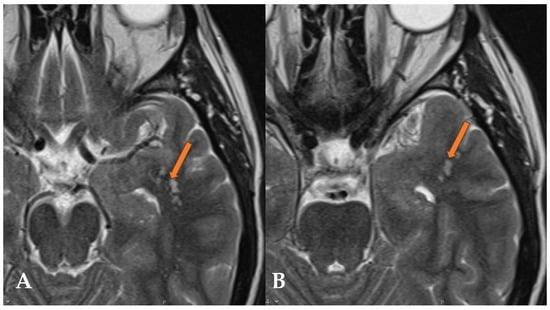

2.2. Case 2